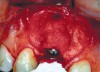

Fig 5. Surgical placement of the implant with bone grafting as necessary.

Figure 5